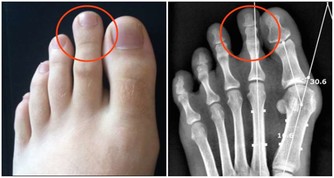

國慶假期前,陳先生去做了一次身體檢查,結果出來后他傻了眼:肝內總脂肪量佔到肝重的10%,輕度脂肪肝。